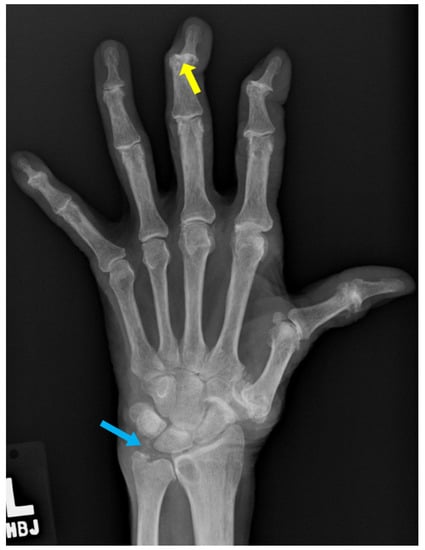

8. Gout